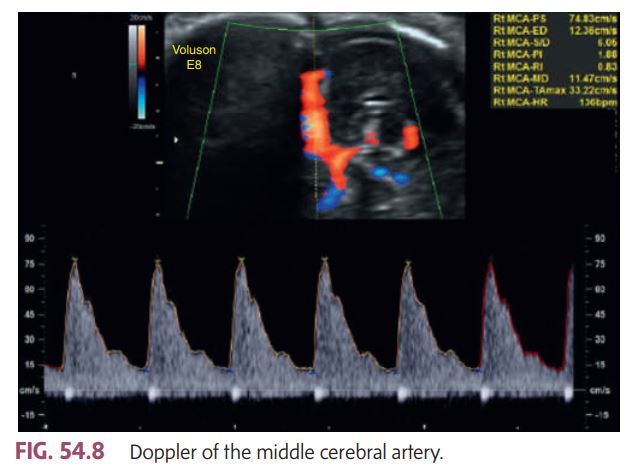

The peak systolic velocity (PSV) shown in the image is 74.83 cm/s, which is within the normal range for most gestational ages.

According to book: a PSV greater than 1.5 multiples of the median (MoM) suggests severe fetal anemia. Since this velocity does not exceed that threshold, it indicates no evidence of fetal anemia.

This MCA Doppler image demonstrates a __________

Normal flow pattern and normal velocity, suggesting no signs of fetal anemia.

Doppler of the middle cerebral artery